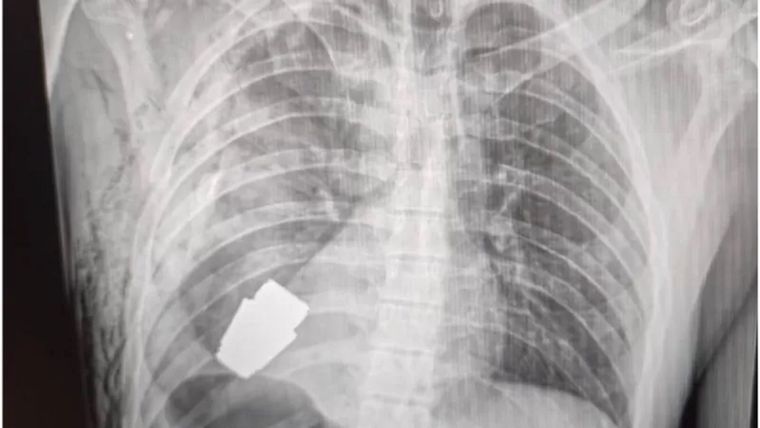

El fragmento de la granada de fabricación rusa que quedó alojado en el cuerpo del soldado tenía cuatro centímetros de diámetro y pesaba 275 gramos.